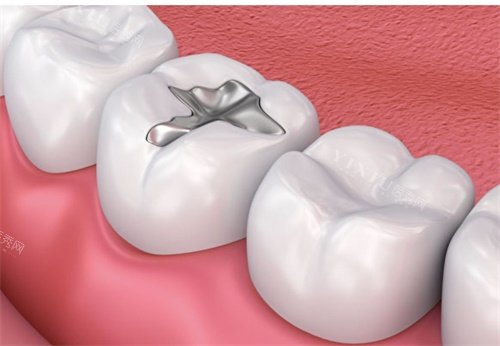

金属合金材料:坚固耐用但有局限

金属合金包括银汞合金和金合金。银汞合金抗压强度高达 300MPa,是后牙咬合面大面积缺损的首要选择材料。它价格相对较低,而且具有较好的耐磨性。然而,银汞合金颜色与天然牙齿差异较大,不够美观,并且存在汞污染的争议。金合金生物稳定性较好,但制作需要特殊设备,价格也比较昂贵。例如,赵先生后牙有较大的龋洞,医生考虑到他后牙咀嚼力大的情况,推荐了银汞合金补牙,使用多年后,补牙部位依然坚固。